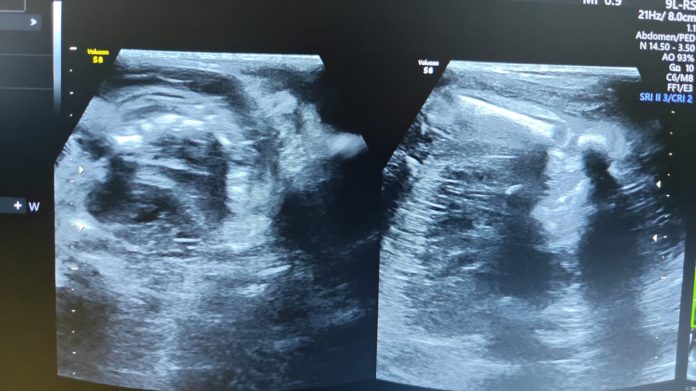

जांच के दौरान कुछ असामान्य संकेत मिलने पर डॉक्टर ने शिशु को अल्ट्रासाउंड के लिए भेजा।अल्ट्रासाउंड जांच में रेडियोलॉजिस्ट डॉ. फारूक़ अरशद ने इस दुर्लभ स्थिति की पहचान की।चिकित्सा विज्ञान में “Fetus in Fetu”एक अत्यंत विरल अवस्था मानी जाती है, जिसमें एक अधूरा विकसित भ्रूण, दूसरे भ्रूण के शरीर के अंदर मौजूद होता है।

विशेषज्ञों के मुताबिक, इस स्थिति की घटना दर लगभग 5 लाख जन्मों में एक मानी जाती है, जबकि विश्वभर में अब तक 200 से भी कम मामले दर्ज किए गए हैं।डॉ. फारूक़ अरशद ने बताया कि इस प्रकार के मामलों की पहचान बेहद सावधानी और उच्च स्तरीय विशेषज्ञता की मांग करती है।